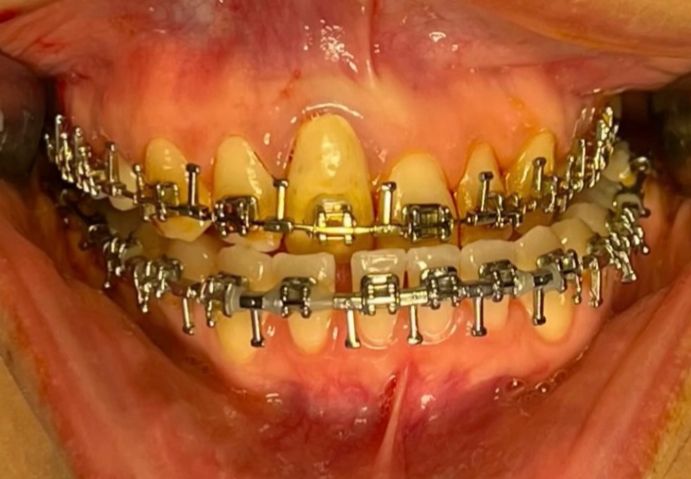

After

Before